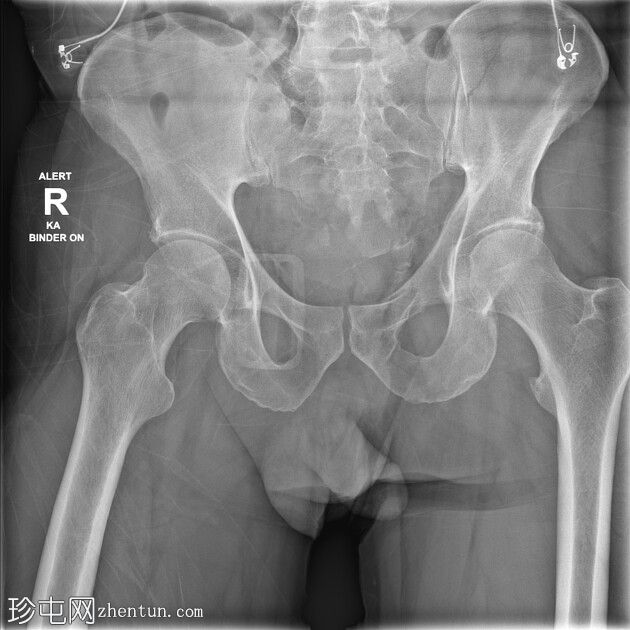

X光片

骨盆固定带在位。左侧耻骨上支和下支轻微移位骨折。髋臼正常。左侧髂骨翼斜形骨折(新月形骨折)延伸至左侧骶髂关节。骶髂关节未见增宽。耻骨联合未见增宽。右侧骶骨在骶髂关节下方骨折。尾骨向左侧脱位。